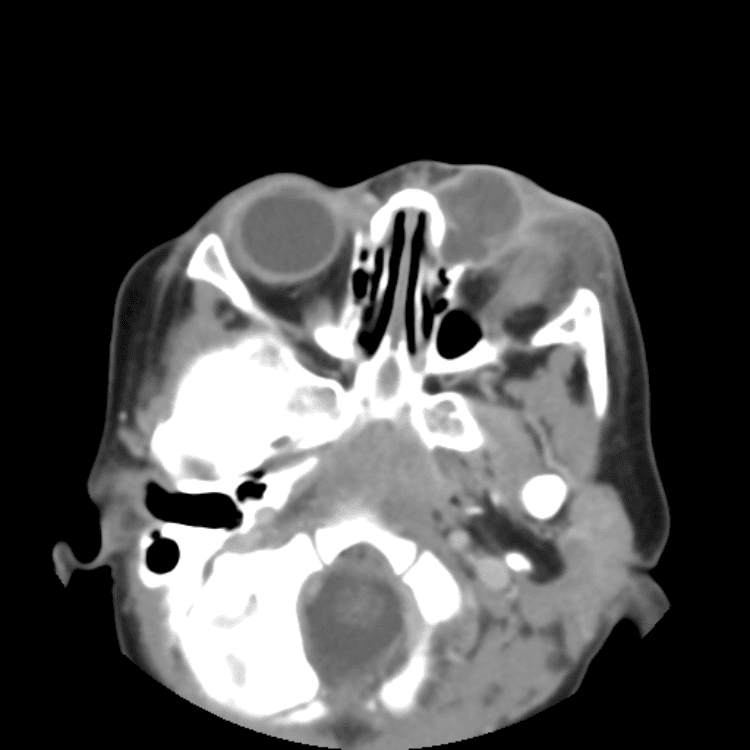

Head and Neck

Simulates call by including subtle or difficult cases and some normals.

27 cases